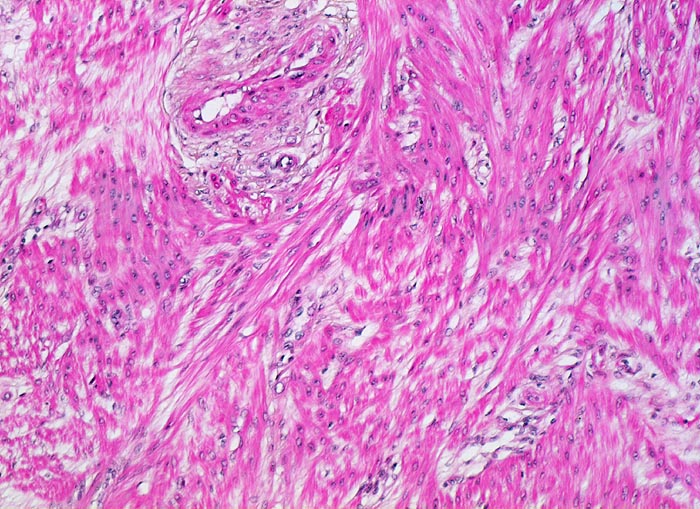

Morphologische Merkmale:

• Myometrium bedeckt von dezidualisiertem Endometriumstroma der Dezidua basalis.

• Invasion des Myometriums durch intermediären extravillösen Trophoblast.

• Fibrinoidschicht.

• Chorionzotten, ein Teil davon verankert mit dem dezidual transformierten Endometrium = Dezidua basalis (Haftzotten).

• Choriondeckplatte.

• Rechts oben Anteile des Chorion laeve.